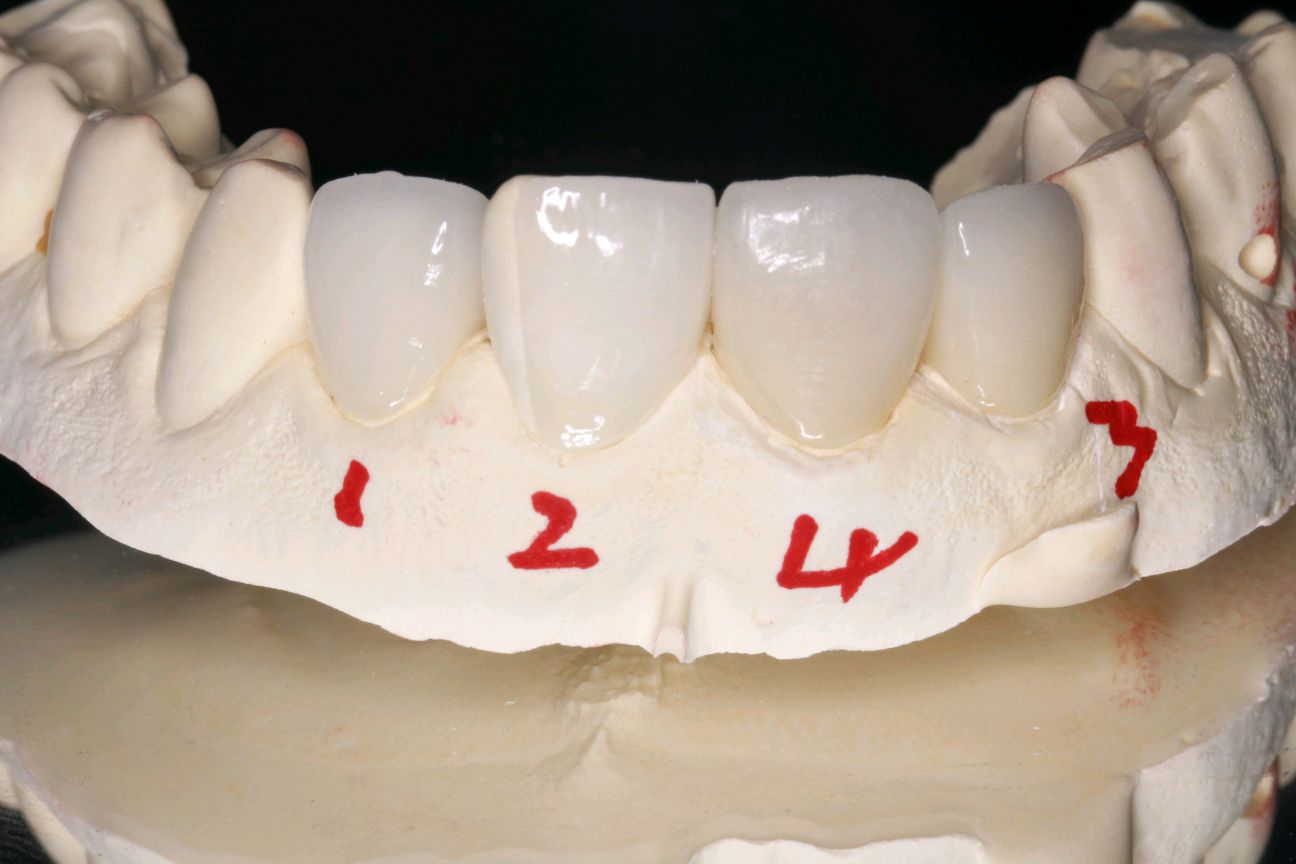

患者女,三十岁,12,11已行根管治疗,未做修复。牙齿发生了变色。其原因是牙齿出现神经炎症或坏死,经过根管治疗后,牙齿会失去来自牙髓的营养供应。这就好比一棵树一旦失去了根系,就会逐渐枯萎一样,慢慢的色泽也会发生变化。死髓的牙齿由于缺乏活力,会逐渐变色,甚至变黑,影响美观。21,23近中龋坏可行全瓷贴面,减少基牙的磨出面积的同时又能更好的恢复牙齿的自然色泽,使牙齿看起来更加健康和美观。

术后